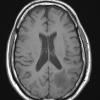

Astrocytoma, IDH-mutant, WHO Grade 2 (3)